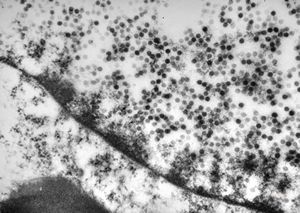

F, 46y. | verruca vulgaris … intranuclear virions